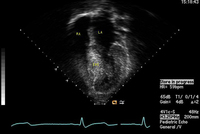

Hypertrophic cardiomyopathy

Apical 4-chamber image demonstrating hypertrophy of the interventricular septum

From the collection of Dr Anji T. Yetman MD, University of Utah; used with permission